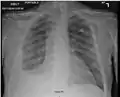

There are three key elements to the diagnosis of silicosis. First, the patient history should reveal exposure to sufficient silica dust to cause this illness. Second, chest imaging (usually chest x-ray) that reveals findings consistent with silicosis. Third, there are no underlying illnesses that are more likely to be causing the abnormalities. Physical examination is usually unremarkable unless there is complicated disease. Also, the examination findings are not specific for silicosis. Pulmonary function testing may reveal airflow limitation, restrictive defects, reduced diffusion capacity, mixed defects, or may be normal (especially without complicated disease). Most cases of silicosis do not require tissue biopsy for diagnosis, but this may be necessary in some cases, primarily to exclude other conditions.

For uncomplicated silicosis, chest x-ray will confirm the presence of small (< 10 mm) nodules in the lungs, especially in the upper lung zones. Using the ILO classification system, these are of profusion 1/0 or greater and shape/size "p", "q", or "r". Lung zone involvement and profusion increases with disease progression. In advanced cases of silicosis, large opacity (> 1 cm) occurs from coalescence of small opacities, particularly in the upper lung zones. With retraction of the lung tissue, there is compensatory emphysema. Enlargement of the hilum is common with chronic and accelerated silicosis. In about 5–10% of cases, the nodes will calcify circumferentially, producing so-called "eggshell" calcification. This finding is not pathognomonic (diagnostic) of silicosis. In some cases, the pulmonary nodules may also become calcified.

Chest X-ray showing uncomplicated silicosis